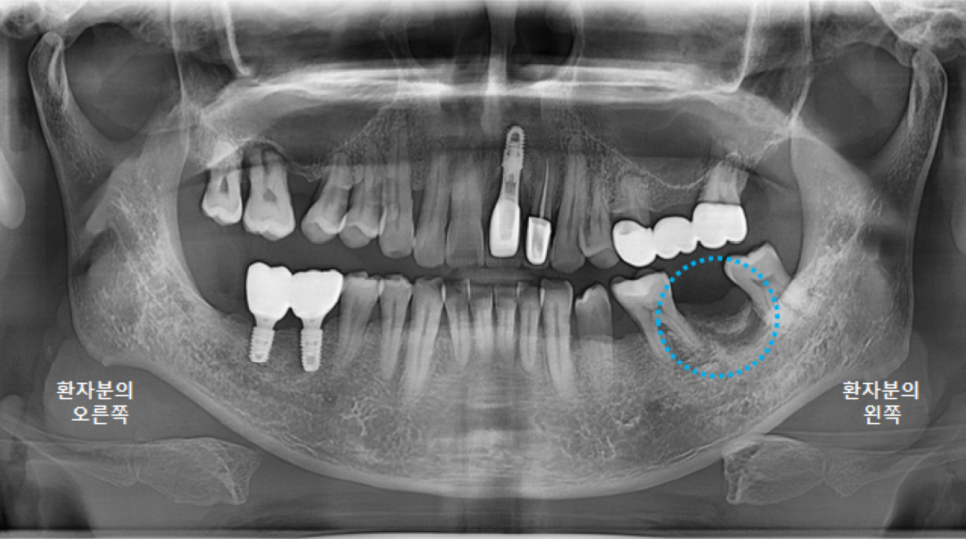

왼쪽아래 큰어금니의 남아있던 뿌리를 제거한지 4개월이 지났습니다.

염증이 너무 심한 상태여서 치유가 빠르지는 않습니다.

뼈가 더 잘 찰 수 있도록, 뼈이식을 진행합니다.

다시 충분히 치유를 기다려봅니다.

5~6개월 정도 예상합니다.

그리고 다시 파노라마 엑스레이를 촬영했습니다.

최상의 컨디션은 아니지만,

어느정도 치유가 되었기에 3차원 CT 촬영 후, 왼쪽아래 큰어금니 임플란트 수술을 진행하도록 합니다.